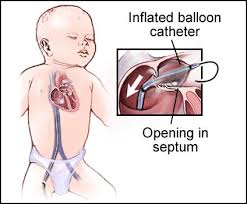

Overview

Package includes:

Days in hospital : 10 to 11 Days (For patient and one attendant)

Days in hotel : 14 Days (For patient and one attendant)

Room type in hospital : Shared

Room type in hotel : Private

Hotel category: Standard

Value added benefits of the VSD Closure:

Ø Doctor consultation charges

Ø Lab tests and diagnostic charges

Ø Room charges inside hospital during the procedure

Ø Surgeon Fee

Ø Nursing charges

Ø Hospital surgery suite charges

Ø Anesthesia charges

Ø Routine medicines and routine consumables (bandages, dressings etc.)

Ø Food and Beverages inside hospital stay for patient and one attendant.

Extra benefits:

ü Interpreter

ü Visa assistance

Ø Site tourism of the city

Ø Follow up with the doctor

Ø Airport pick up and drop

Ø Free online consultation with the doctor

Ø Priority appointments with the doctor

Ø Room upgrade from sharing to private

Overview

Package includes:

Days in hospital : 10 to 11 Days (For patient and one attendant)

Days in hotel : 14 Days (For patient and one attendant)

Room type in hospital : Shared

Room type in hotel : Private

Hotel category: Standard

Value added benefits of the ASD Closure:

Ø Doctor consultation charges

Ø Lab tests and diagnostic charges

Ø Room charges inside hospital during the procedure

Ø Surgeon Fee

Ø Nursing charges

Ø Hospital surgery suite charges

Ø Anesthesia charges

Ø Routine medicines and routine consumables (bandages, dressings etc.)

Ø Food and Beverages inside hospital stay for patient and one attendant.

Extra benefits:

ü Interpreter

ü Visa assistance

Ø Site tourism of the city

Ø Follow up with the doctor

Ø Airport pick up and drop

Ø Free online consultation with the doctor

Ø Priority appointments with the doctor

Ø Room upgrade from sharing to private